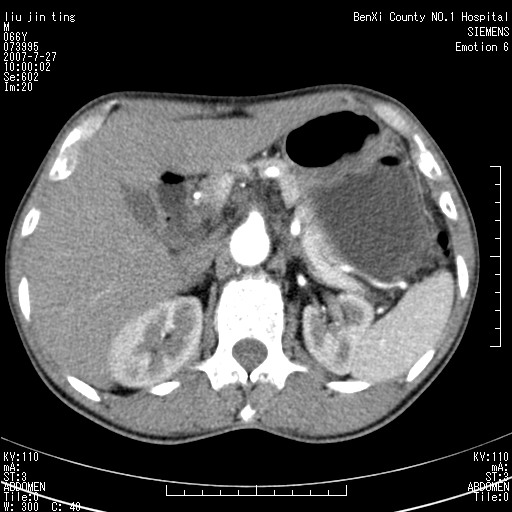

腹痛,背痛,无恶心呕吐,不黄,彩超示胰腺钩癌,ct扫描病灶平扫30-40hu,增强后动脉期40--60hu,静脉期50-68hu,真的是钩突上的么?您要试一试么?

我觉得不是胰腺的病变,后腹膜占位,淋巴结?肿瘤?

钩突是正常的,只见腹膜后淋巴结的肿大,考虑淋巴瘤或转移可能。

腹膜后占位性病变,首先考虑肿大淋巴结。

后腹膜肿块,包围血管,考虑淋巴恶性病变,淋巴瘤或转移。